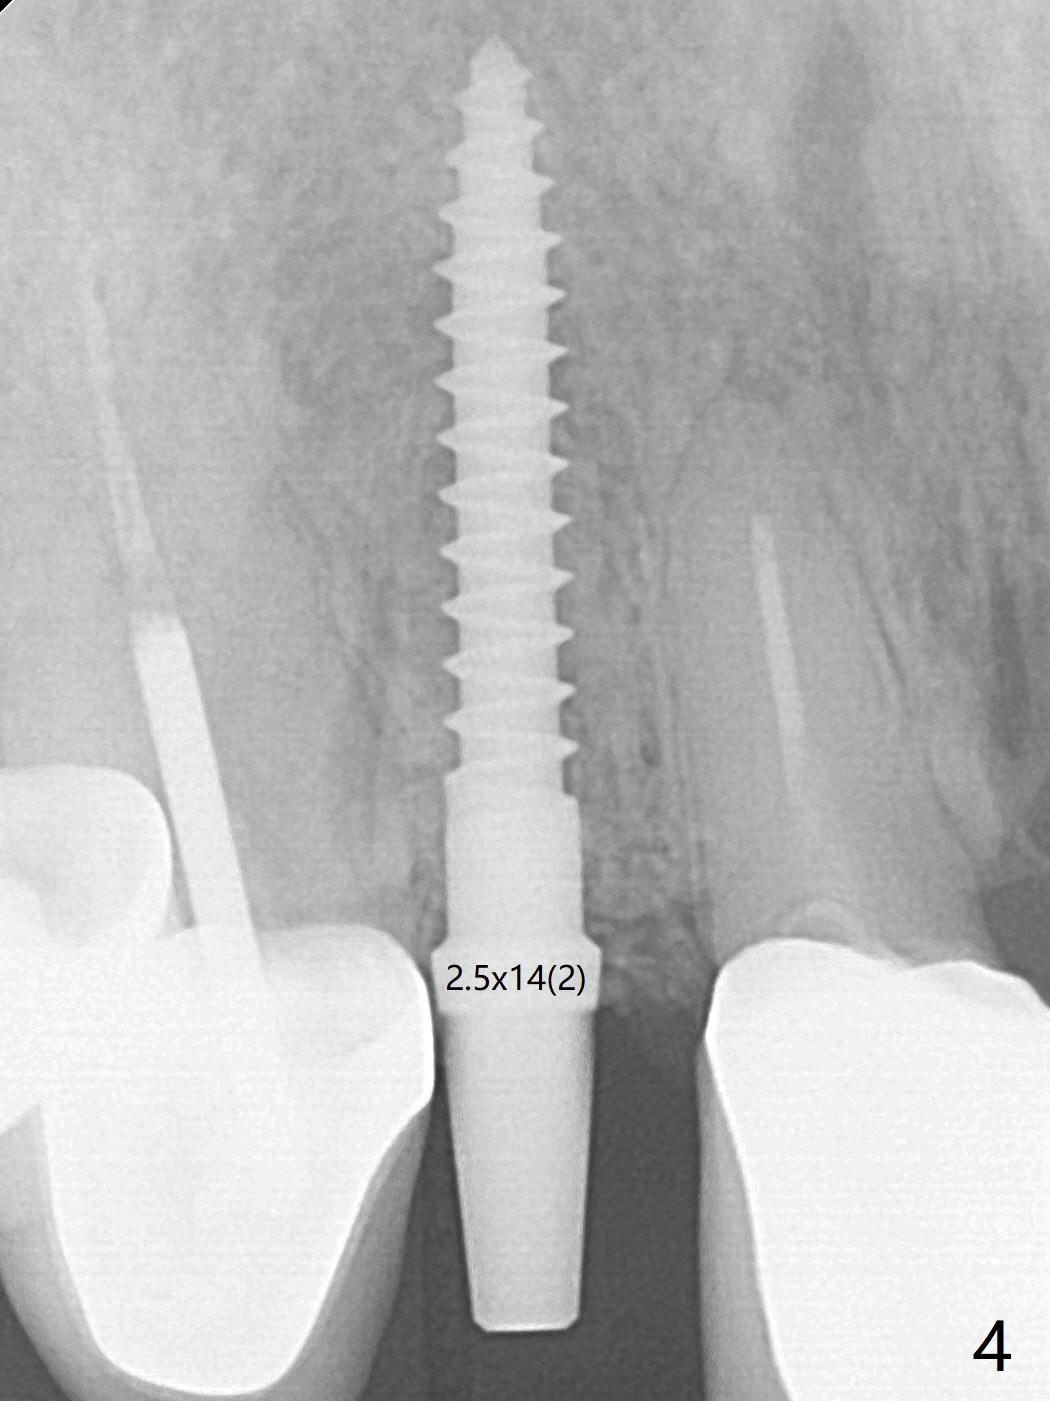

Because of the long crowns of the neighboring teeth, it is difficult to remove the apical portion of the root, including gutta percha with surgical handpiece (Fig.3 * (1.2 mm drill for 12 mm)) for socket shield. To avoid the perspective implant touching socket shield, initial osteotomy is palatal. When a 2 mm drill is being used, the coronal end of the palatal plate starts to perforate. A 2.5x14 mm 1-piece implant is placed with 30 Ncm (Fig.4). The teeth #8 and 9 fracture (an implant is placed at #8 and bone graft at #9), while the implant at #7 is osteointegrating (Fig.7). In fact the shield is exposed without symptom.